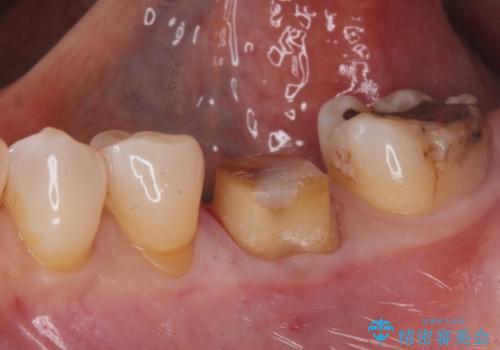

- 奥歯の銀の詰め物が取れたとの事で来院。

詰め物の下に虫歯ができて銀歯が取れてしまった事が予想されます。

白い詰め物でやり直しをしても歯質が薄くなり割れてしまうリスクがあるために、

割れるリスクの少ないジルコニアクラウンにて治療しました。